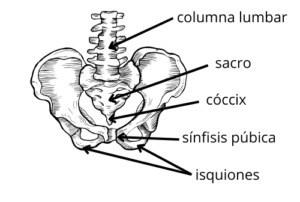

Para comprender esto adecuadamente, primero debemos aclarar ciertos aspectos anatómicos de la pelvis.

En la parte frontal de la pelvis, podemos palpar la sínfisis púbica. Se trata de una articulación fibrocartilaginosa que conecta los dos huesos del pubis y se ubica en la línea media del cuerpo, justo debajo del abdomen. En la parte posterior, encontramos el cóccix. Este es un hueso situado en la parte inferior de la columna vertebral, justo debajo del sacro. Por último, localizamos los isquiones, que son los huesos en los que te apoyas al sentarte en una silla.

Todas las estructuras que mencioné son puntos de anclaje para los músculos del suelo pélvico.